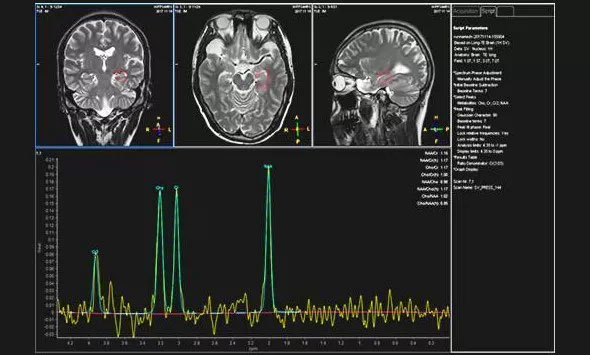

▲患者异常的波谱图

近日,为求进一步治疗,患者就诊于上海蓝十字脑科医院。为完善相关检查,医院为袁女士进行了头部MRI增强扫描,检查结果与之前的影像检查一致。为了进一步明确病灶区,医院为患者进行24小时脑电监测,据脑电监测主任崔丽华介绍,患者为异常视频脑电图,左侧额极、左侧颞叶多量尖慢波并发,监测期间患者癫痫还发作了3次。